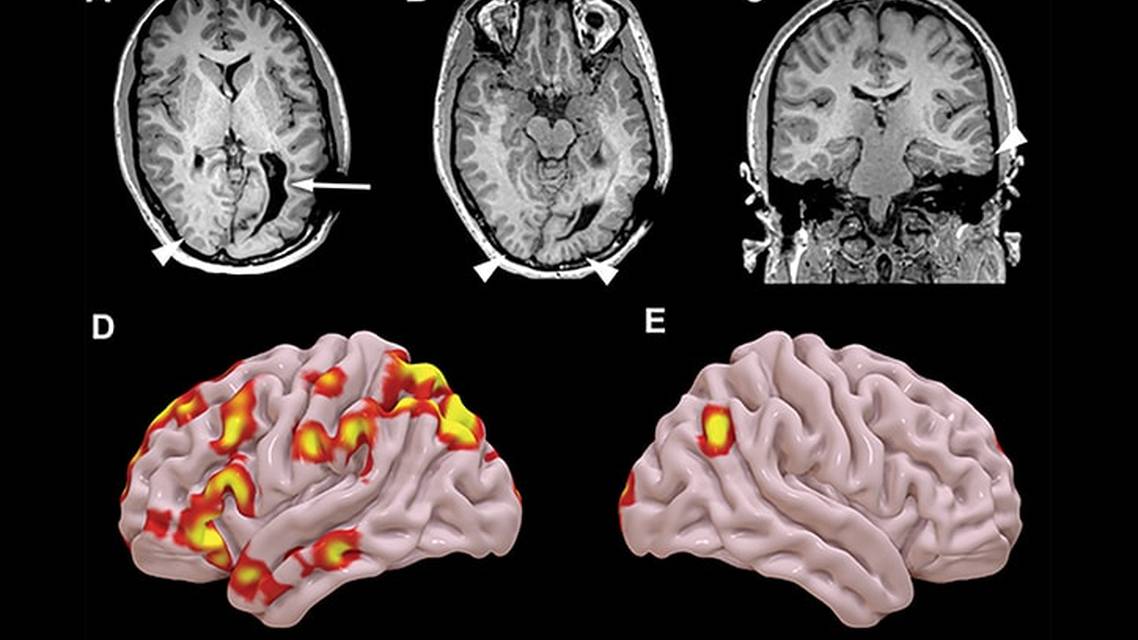

Determining the proper treatment in DRE requires diagnosis and characterization of any and all seizures in each individual. This is first done using scalp videoEEG and neuroimaging, typically an epilepsy protocol MRI (3T or 7T). Other noninvasive tests can also be performed when clinically indicated and available. These include magnetoencephalography (MEG), positron emission tomography (PET)/CT, PET/MRI, or ictal SPECT.2,4,8 Although these studies can help localize the epileptogenic zone, each has limitations in sensitivity and specificity regarding localizing seizure foci. If the results of noninvasive studies are concordant, intracranial videoEEG is typically not needed, and a treatment plan can be initiated.6-8

In some cases, noninvasive testing is not concordant or does not localize seizure foci well enough to develop a proper treatment plan; however, there is enough clinical data to support focal epilepsy (or possibly more than one focus) that is surgically amenable to resection, ablation, or neurostimulation. In these situations, intracranial videoEEG is performed using depth electrodes and or subdural grids or strips that are implanted to localize the epileptogenic zone(s) more accurately.2,8 See Figure 4 for a stepwise presurgical approach with a particular focus on candidates for neurostimulation.

In this case, intracranial videoEEG monitoring was pursued to better pinpoint presumed focal epilepsy in the left hemisphere. Ultimately, at least 2 broad epileptogenicity areas were found, making BA a candidate for neurostimulation therapy.